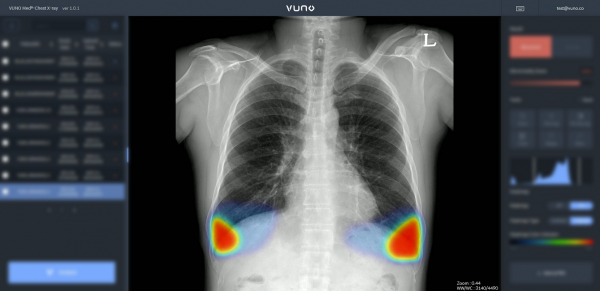

뷰노메드 체스트 엑스레이, 서울아산병원 건강증진센터에 도입

뷰노는 최근 인공지능 기반 흉부 엑스레이 영상 판독 보조 솔루션 ‘뷰노메드 체스트 엑스레이(VUNO Med-Chest X-ray)’가 서울아산병원 건강증진센터에 도입돼 활용되고 있다고 19일 밝혔다.

뷰노메드 체스트 엑스레이는 ▷결절 ▷경화 ▷기흉 ▷삼출 ▷간질성 음영 등 주요 흉부 촬영 영상 의 이상소견을 탐지하고, 병변 부위를 정확히 제시해 의료진 판독을 돕는 인공지능 솔루션이다.

해당 솔루션은 지난 6월 말 본 센터에 도입돼 수검자들의 흉부 촬영 검사에 활용되면서, 의료진의 진단을 보다 보조하고 있는 것으로 알려졌다.

흉부 영상 촬영은 건강검진에서 가장 촬영 빈도가 높은 검사 중 하나로, 해당 영상 판독에 뷰노메드 체스트 엑스레이가 활용되면서, 의료진의 업무 효율성 및 정확도 개선에 도움을 주고 있는 것으로 알려졌다.

해당 솔루션 활용 시 흉부촬영 영상에서 유소견이 있는 증례들을 먼저 판독하도록 보조해, 폐렴이나 종괴 등 병변이 있는 경우 신속한 추후 조치가 가능하다.

김현준 뷰노 대표는 “풍부한 임상 경험을 기반으로 수검자들에게 전문적인 건강검진 서비스를 제공하는 서울아산병원 건강증진센터에 뷰노메드 체스트 엑스레이가 도입돼 매우 기쁘다”라며 “이번 도입을 통해 자사 제품이 본 센터 의료진의 영상 판독 효율성과 정확도를 향상하여 보다 우수한 건강검진 서비스를 제공하는데 도움이 되도록 최선을 다하겠다”고 말했다.